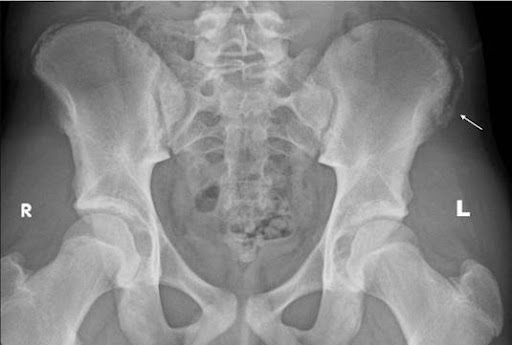

The below X-ray (2) and ultrasound images are from a young teen footballer with an acute, painful ‘pop’ over the high left lateral hip on landing from a jump.

He struggled to bear weight and retired. Examination revealed him unable to single leg squat, Tensor Fascia Lata loading and oblique crunches were sore; exquisitely tender with swelling over 8cm of the iliac crest to the anterior superior iliac spine.

Figure 8 and 9 revealed avulsion of the iliac crest apophysis – rare!!

Figure 8 – AP pelvis xray

Figure 9 – Ultrasound iliac crest